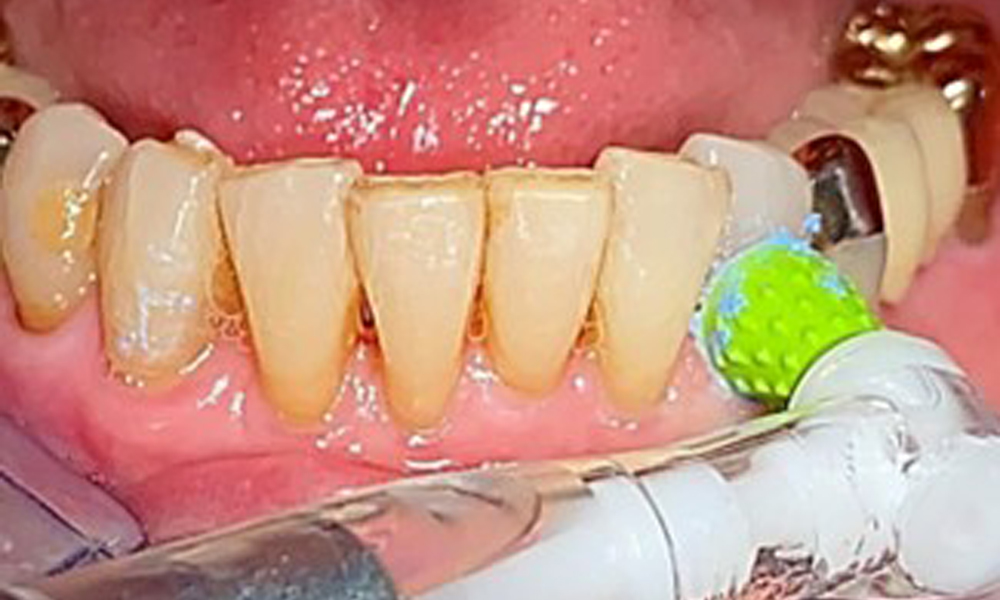

Für die Restaurationsränder und Zahnzwischenräume und Implantatoberflächen kann das Pulverstrahlgerät mit einem niedrig-abrasiven Pulver zum Einsatz zur Entfernung von Biofilm kommen (Abb. 12). Durch selektives Polieren (Abb. 13) sollte eine Glättung aller weniger sensiblen Bereiche erfolgen, da die bakterielle Wiederanhaftung reduziert wird. (9)

Selektives Polieren in Rg. 33 (hier Proxeo Twist, W&H)

Abb. 13: Selektives Polieren in Rg. 33 (hier Proxeo Twist, W&H)

Air Polishing (hier: Proxeo Aura, W&H) an einem Implantat

Abb. 12: Air Polishing (hier: Proxeo Aura, W&H) an einem Implantat